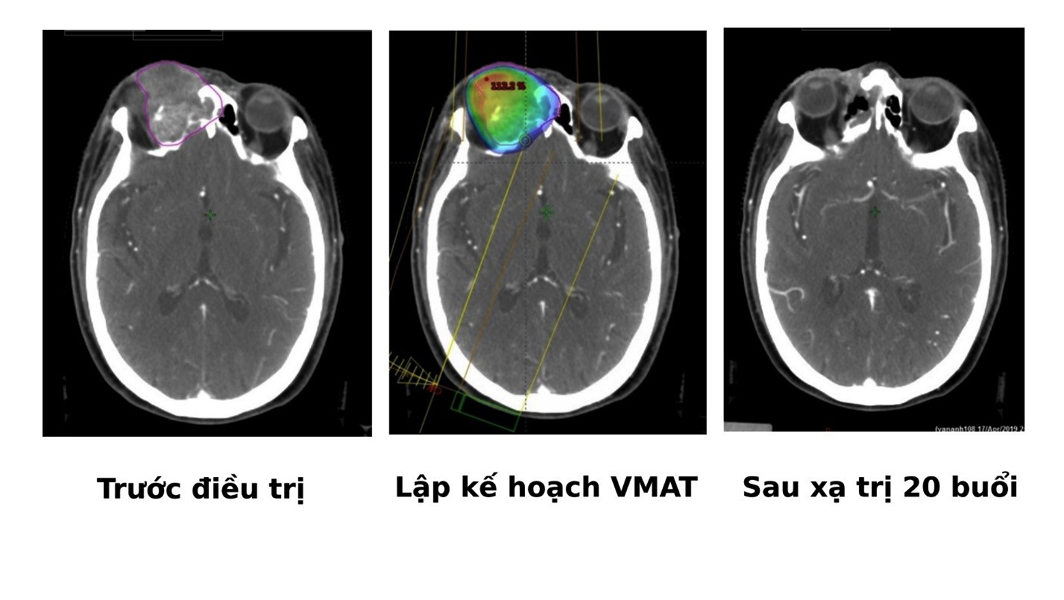

VMAT là kỹ thuật xạ trị điều biến liều kỹ thuật số kết hợp với kỹ thuật hình ảnh CT4D, nhằm định vị chính xác hình dạng và kích thước khối u, từ đó có thể tính toán liều xạ tối ưu nhất để tia xạ tiêu diệt được khối u mà không phải làm tổn hại mô lành xung quanh, nhờ vậy mà hạn chế tối đa các tác dụng phụ ở bệnh nhân.

Theo Bác Sĩ Basma M’Barek, thời gian qua nhiều bệnh nhân ung thư vòm hầu và thanh quản nhờ điều trị bằng kỹ thuật VMAT tại Trung tâm điều trị Ung thư Hy vọng bệnh viện FV đã đạt được hiệu quả điều trị tối ưu, vẫn bảo tồn được các mô lành xung quanh bệnh nhân, sau điều trị có thể nói chuyện ăn uống bình thường đảm bảo chất lượng sống.